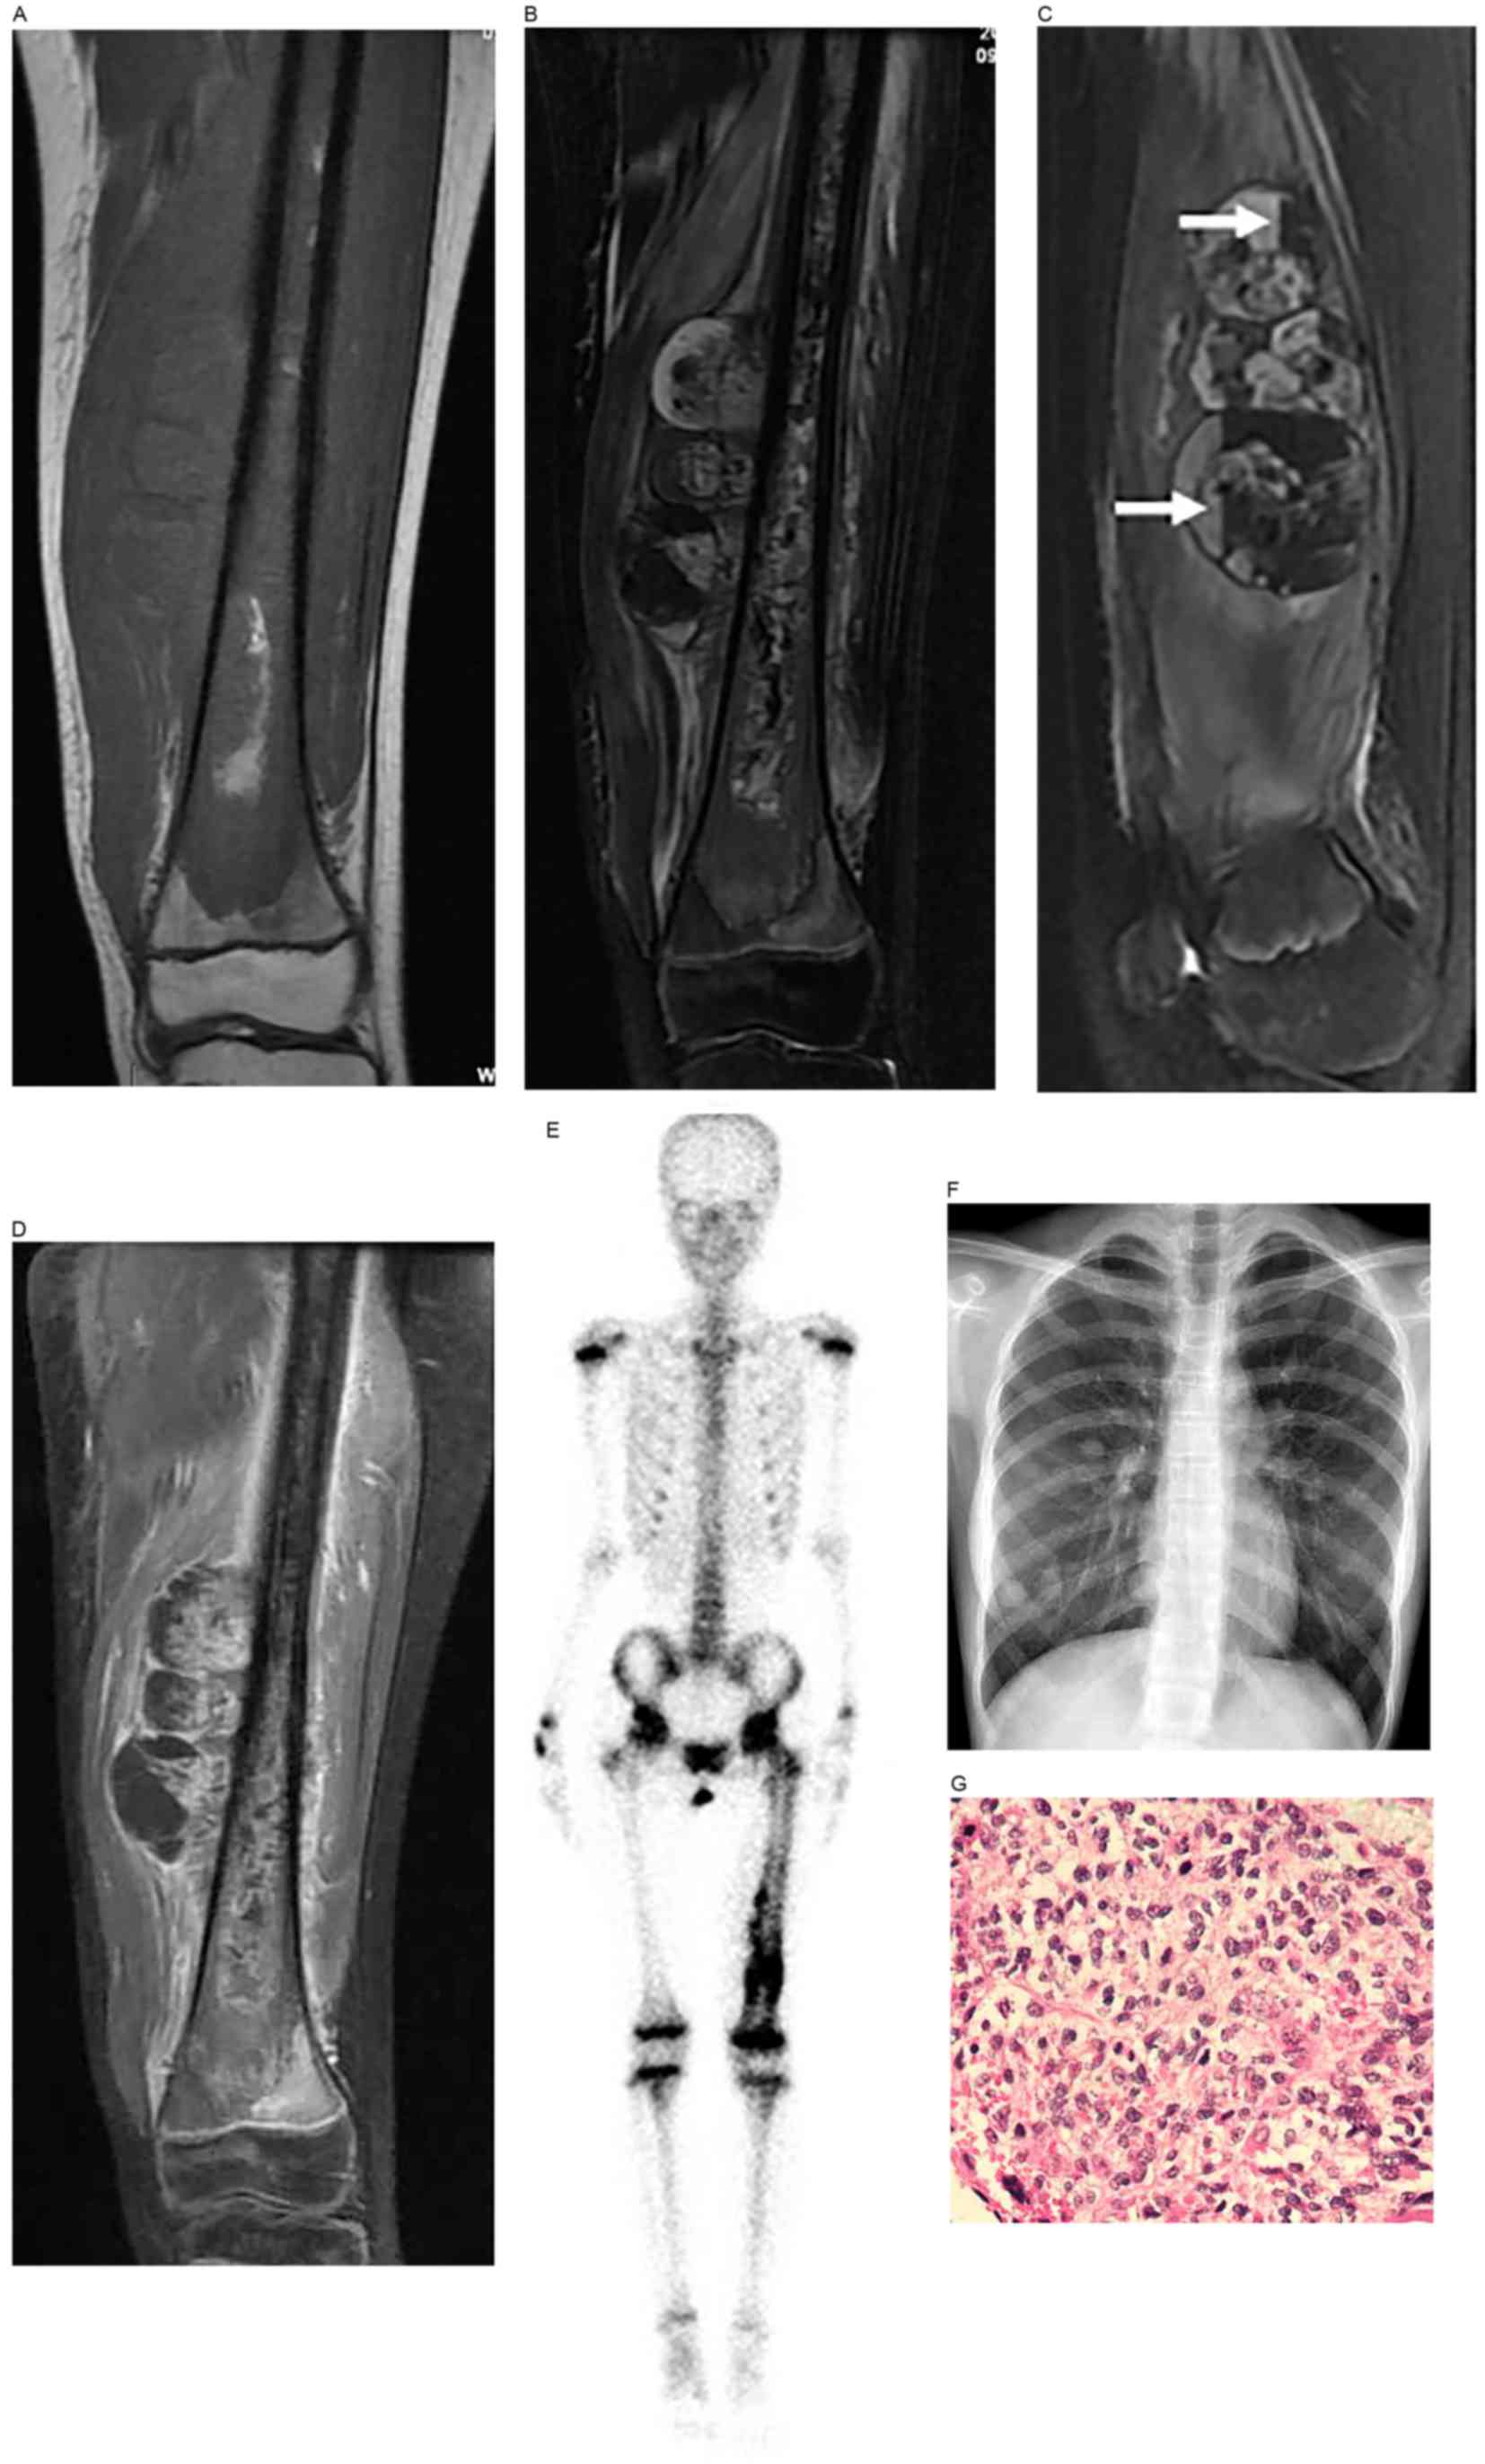

Frontiers Microwave Ablation Of Primary Malignant Pelvic Bone Tumors Surgery

Frontiers Microwave Ablation Of Primary Malignant Pelvic Bone Tumors Surgery from www.frontiersin.org